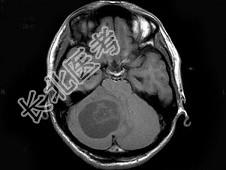

单项选择题男,33岁, 阵发性头痛伴呕吐行走不稳1个月,MRI平扫及增强扫描如图, 最可能的诊断是 ( )

A、右小脑星形细胞瘤

B、右小脑脓肿

C、右小脑血管母细胞瘤

D、转移瘤